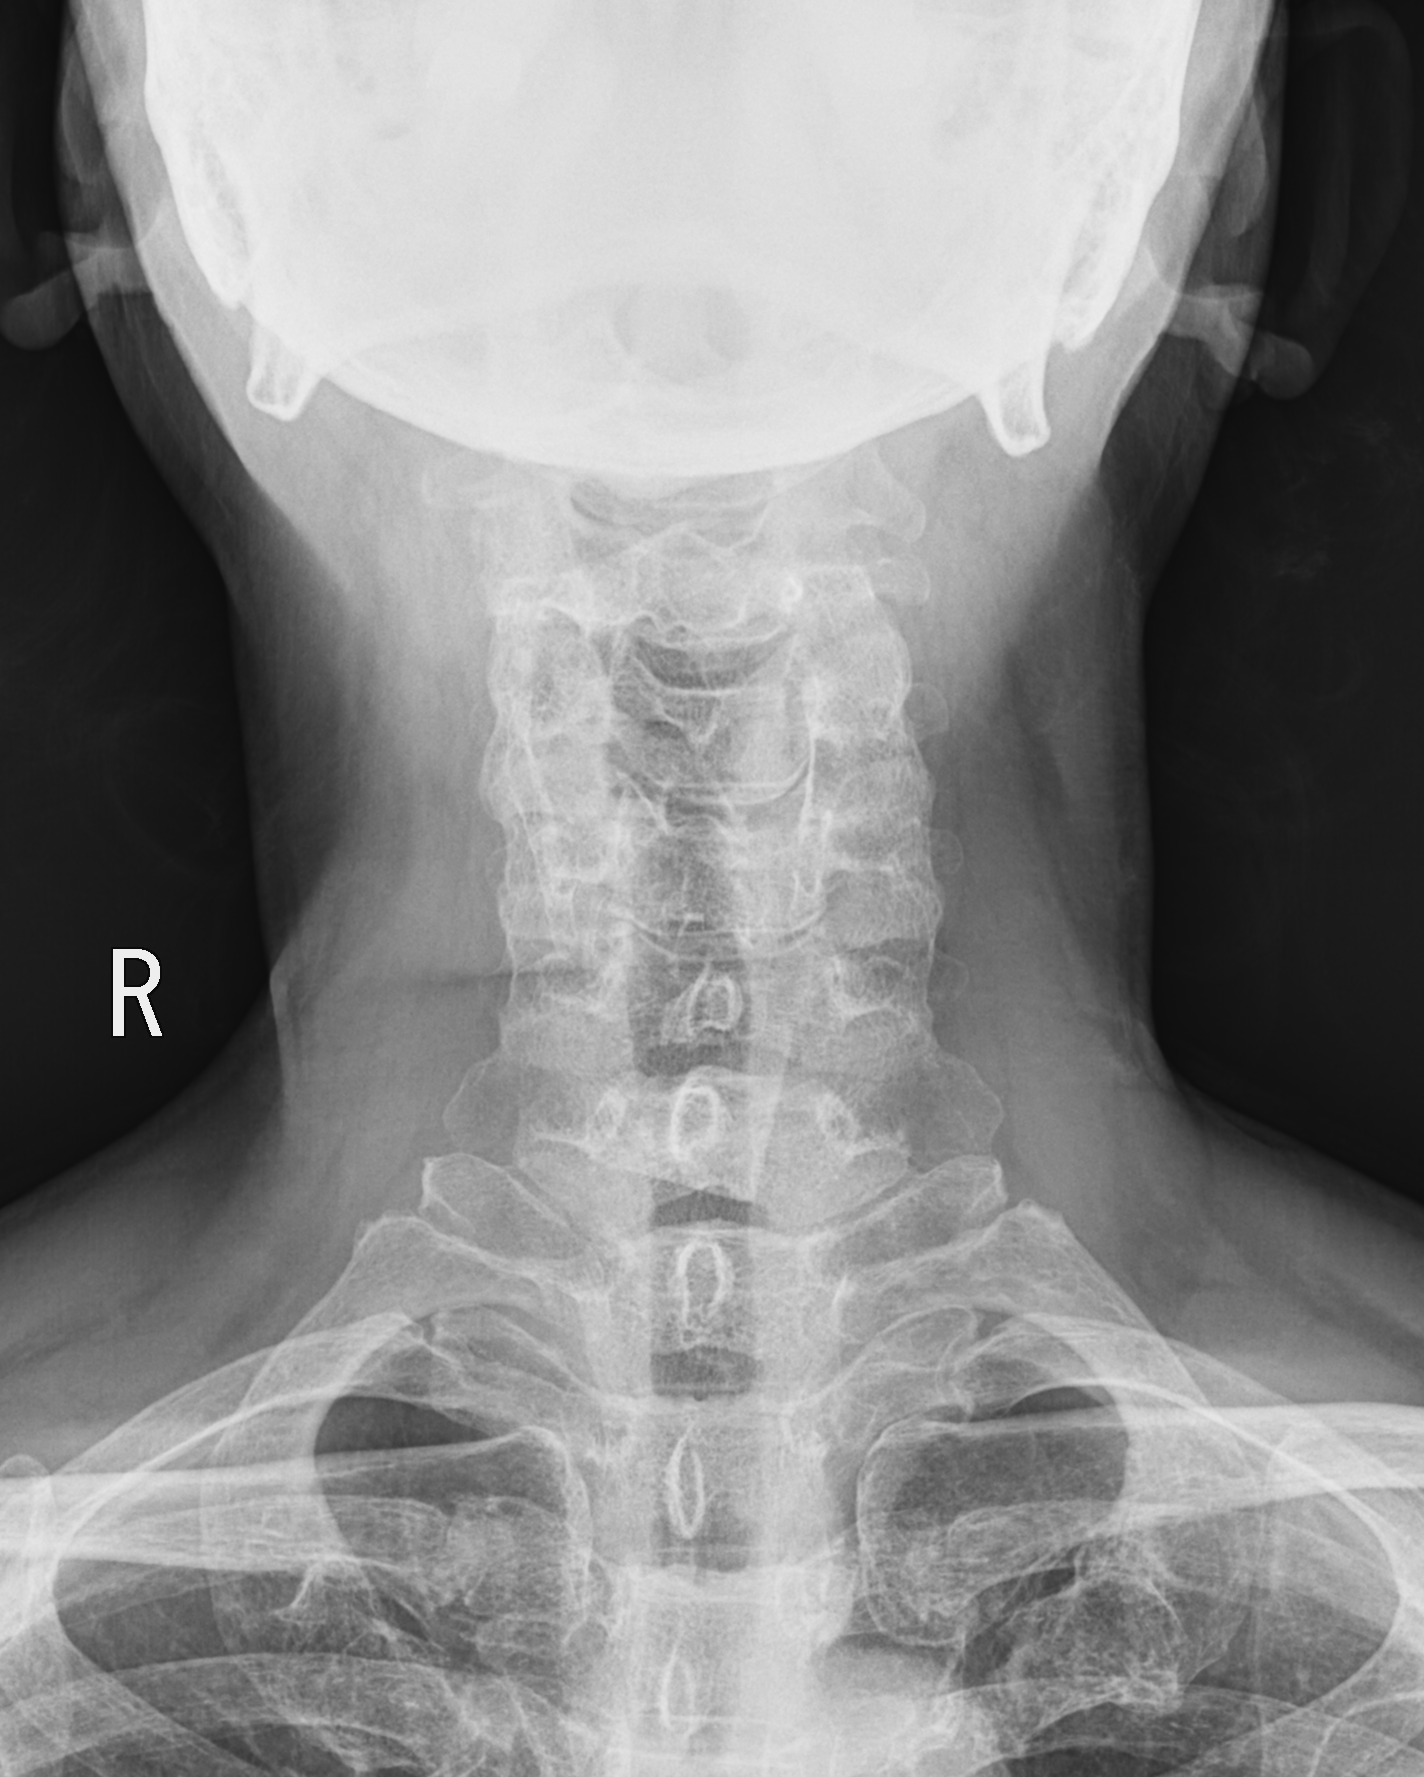

이물의 위치를 확정할 수 없으므로, 목부터 식도, 위장까지 확인하기 위해 흉부 x ray와 함께 경추 x ray(앞뒤와 측면)를 함께 촬영하였다.

예상과는 달리 chest PA, neck AP x ray 사진에서는 이물이 잘 보이지 않았다.